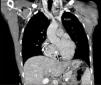

A 31-year-old male presented with alternating bifascicular block with symptomatic complete atrioventricular block and a normal echocardiogram. A permanent pacemaker was implanted through the left subclavian vein. Upon inserting the guidewire, a single persistent left superior vena cava (PLSVC) was identified and verified using phlebography and tomography. The PLSVC flows into the coronary sinus (CS), and into the right atrium (RA). The atrial and right ventricular (RV) active fixation electrodes were implanted retrogradely through the CS (see Figs. 1 and 2).